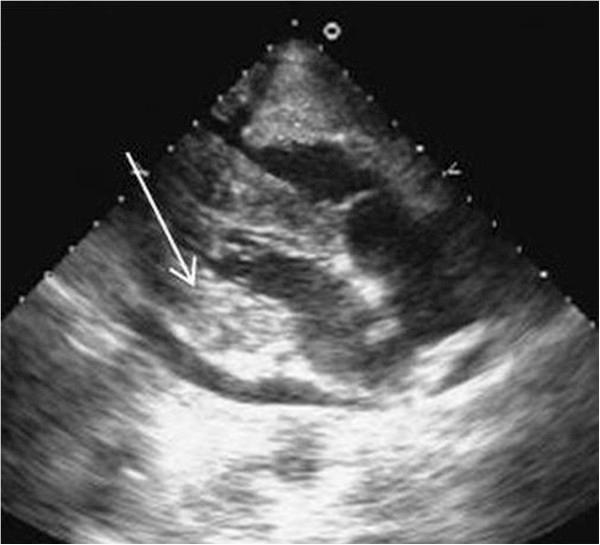

Metastatic involvement of the heart is a rare occurrence and remains undiagnosed until autopsy. In some instances, patients may have cardiac symptoms, leading to ante-mortem diagnosis. Although most primary cancers have been documented to metastasize to heart, the existing literature on cancers of upper aero-digestive tract is an exception, with only a few reports. We report four cases of upper aero-digestive tract cancers, three of which arise from oral cavity, one from lower esophagus, metastasising to the myocardium, detected on 18 F - Fluoro-deoxy-glucose Positron Emission Tomography/Computed Tomography (FDG PET/CT) study , in the absence of related symptoms.

心脏转移受累较为罕见,直至尸检时才得以诊断。在某些情况下,患者可能会出现心脏症状,从而得以生前诊断。尽管大多数原发性癌症都有转移至心脏的记录,但关于上消化道癌症的现有文献却是个例外,仅有少数报道。我们报告了4例上消化道癌症,其中3例起源于口腔,1例起源于食管下段,在没有相关症状的情况下,经18F-氟脱氧葡萄糖正电子发射断层扫描/计算机断层扫描(FDG PET/CT)检查发现转移至心肌。